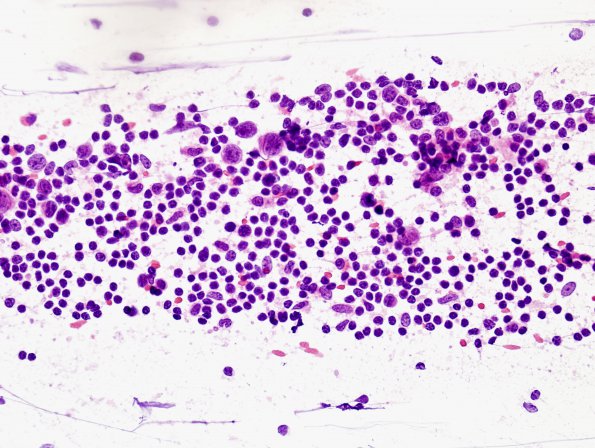

Intraoperative smear preparation shows numerous lymphocytes as well as a few large germinoma cells (H&E).